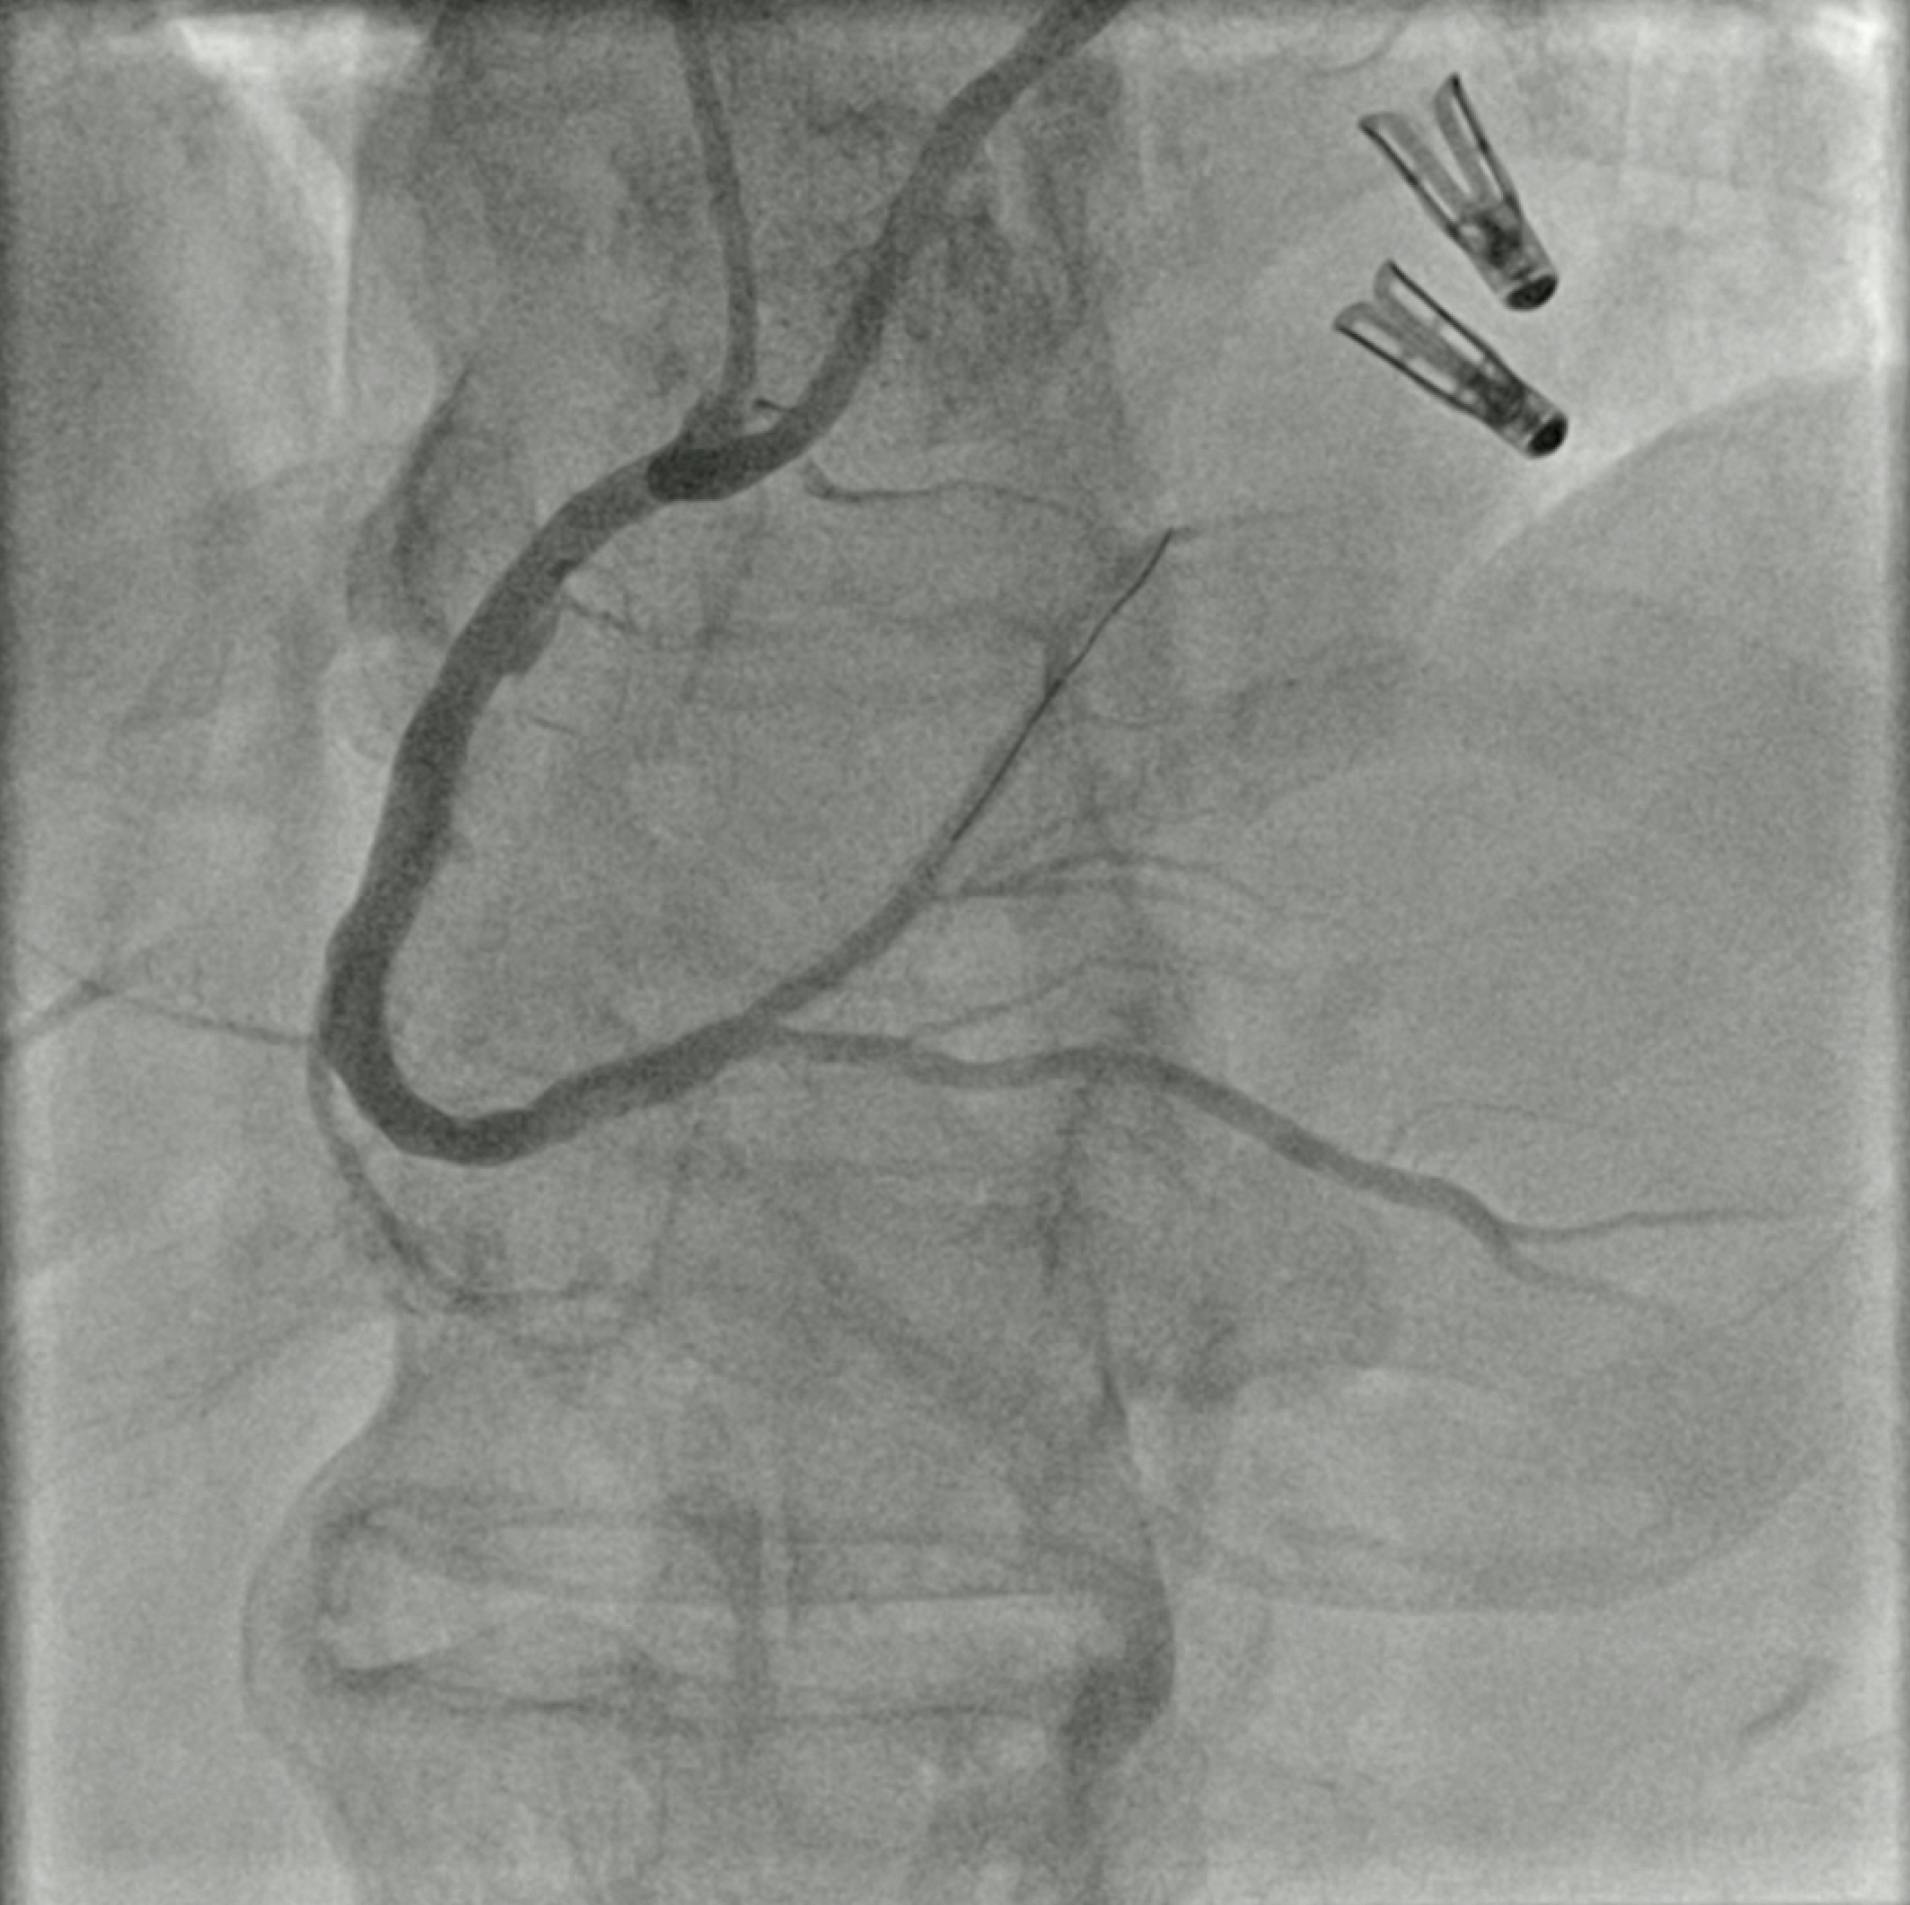

After administration of a loading dose of ticagrelor (180 mg), the occlusion site was successfully crossed with a workhorse guidewire. Sustained mechanical thrombectomy was performed using the Indigo CAT RX aspiration system (Figure 2). The main advantages of this innovative technology in the life-threatening setting of STEMI are the simplicity of setup and ease of use, which allows rapid removal of thrombus and identification of the underlying culprit lesion, thereby facilitating PCI and restoring the epicardial anterograde flow with minimal blood loss. In addition, the 5.3-F Indigo CAT RX catheter is a 6-F–compatible device that navigates easily through tortuous anatomies and allows easy access to distal coronary vessels. After one pass, the intracoronary thrombus was successfully removed (Figure 3) uncovering an underlying significant proximal and mid LAD stenosis (Figure 4). The lesion was subsequently predilated using noncompliant and cutting balloons, followed by a hybrid PCI approach using a newer-generation drug-eluting stent in the proximal LAD and a sirolimus-coated balloon in the mid-LAD.

Figure 2. Coronary angiogram showing the advancement of the Indigo CAT RX aspiration catheter in the proximal LAD.